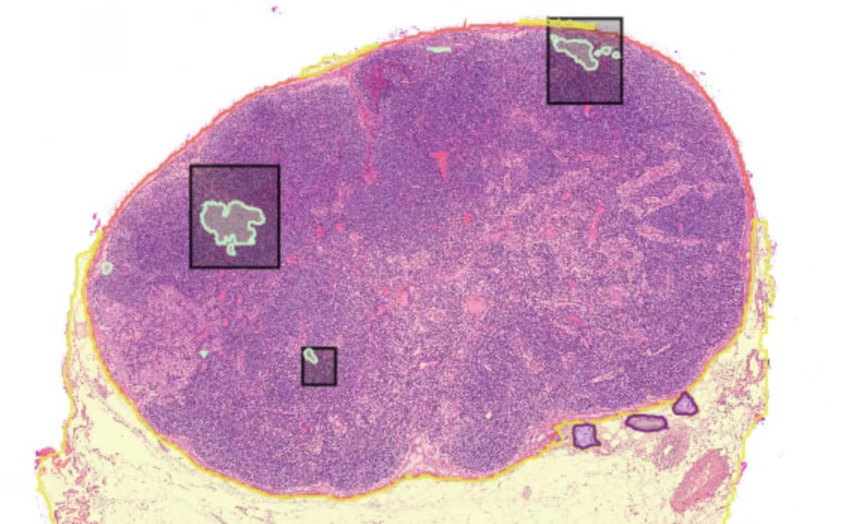

AI-assisted lymph node screening and metastasis detection in whole slide images, enabling automated N-staging for multi-cancer pathology workflows.